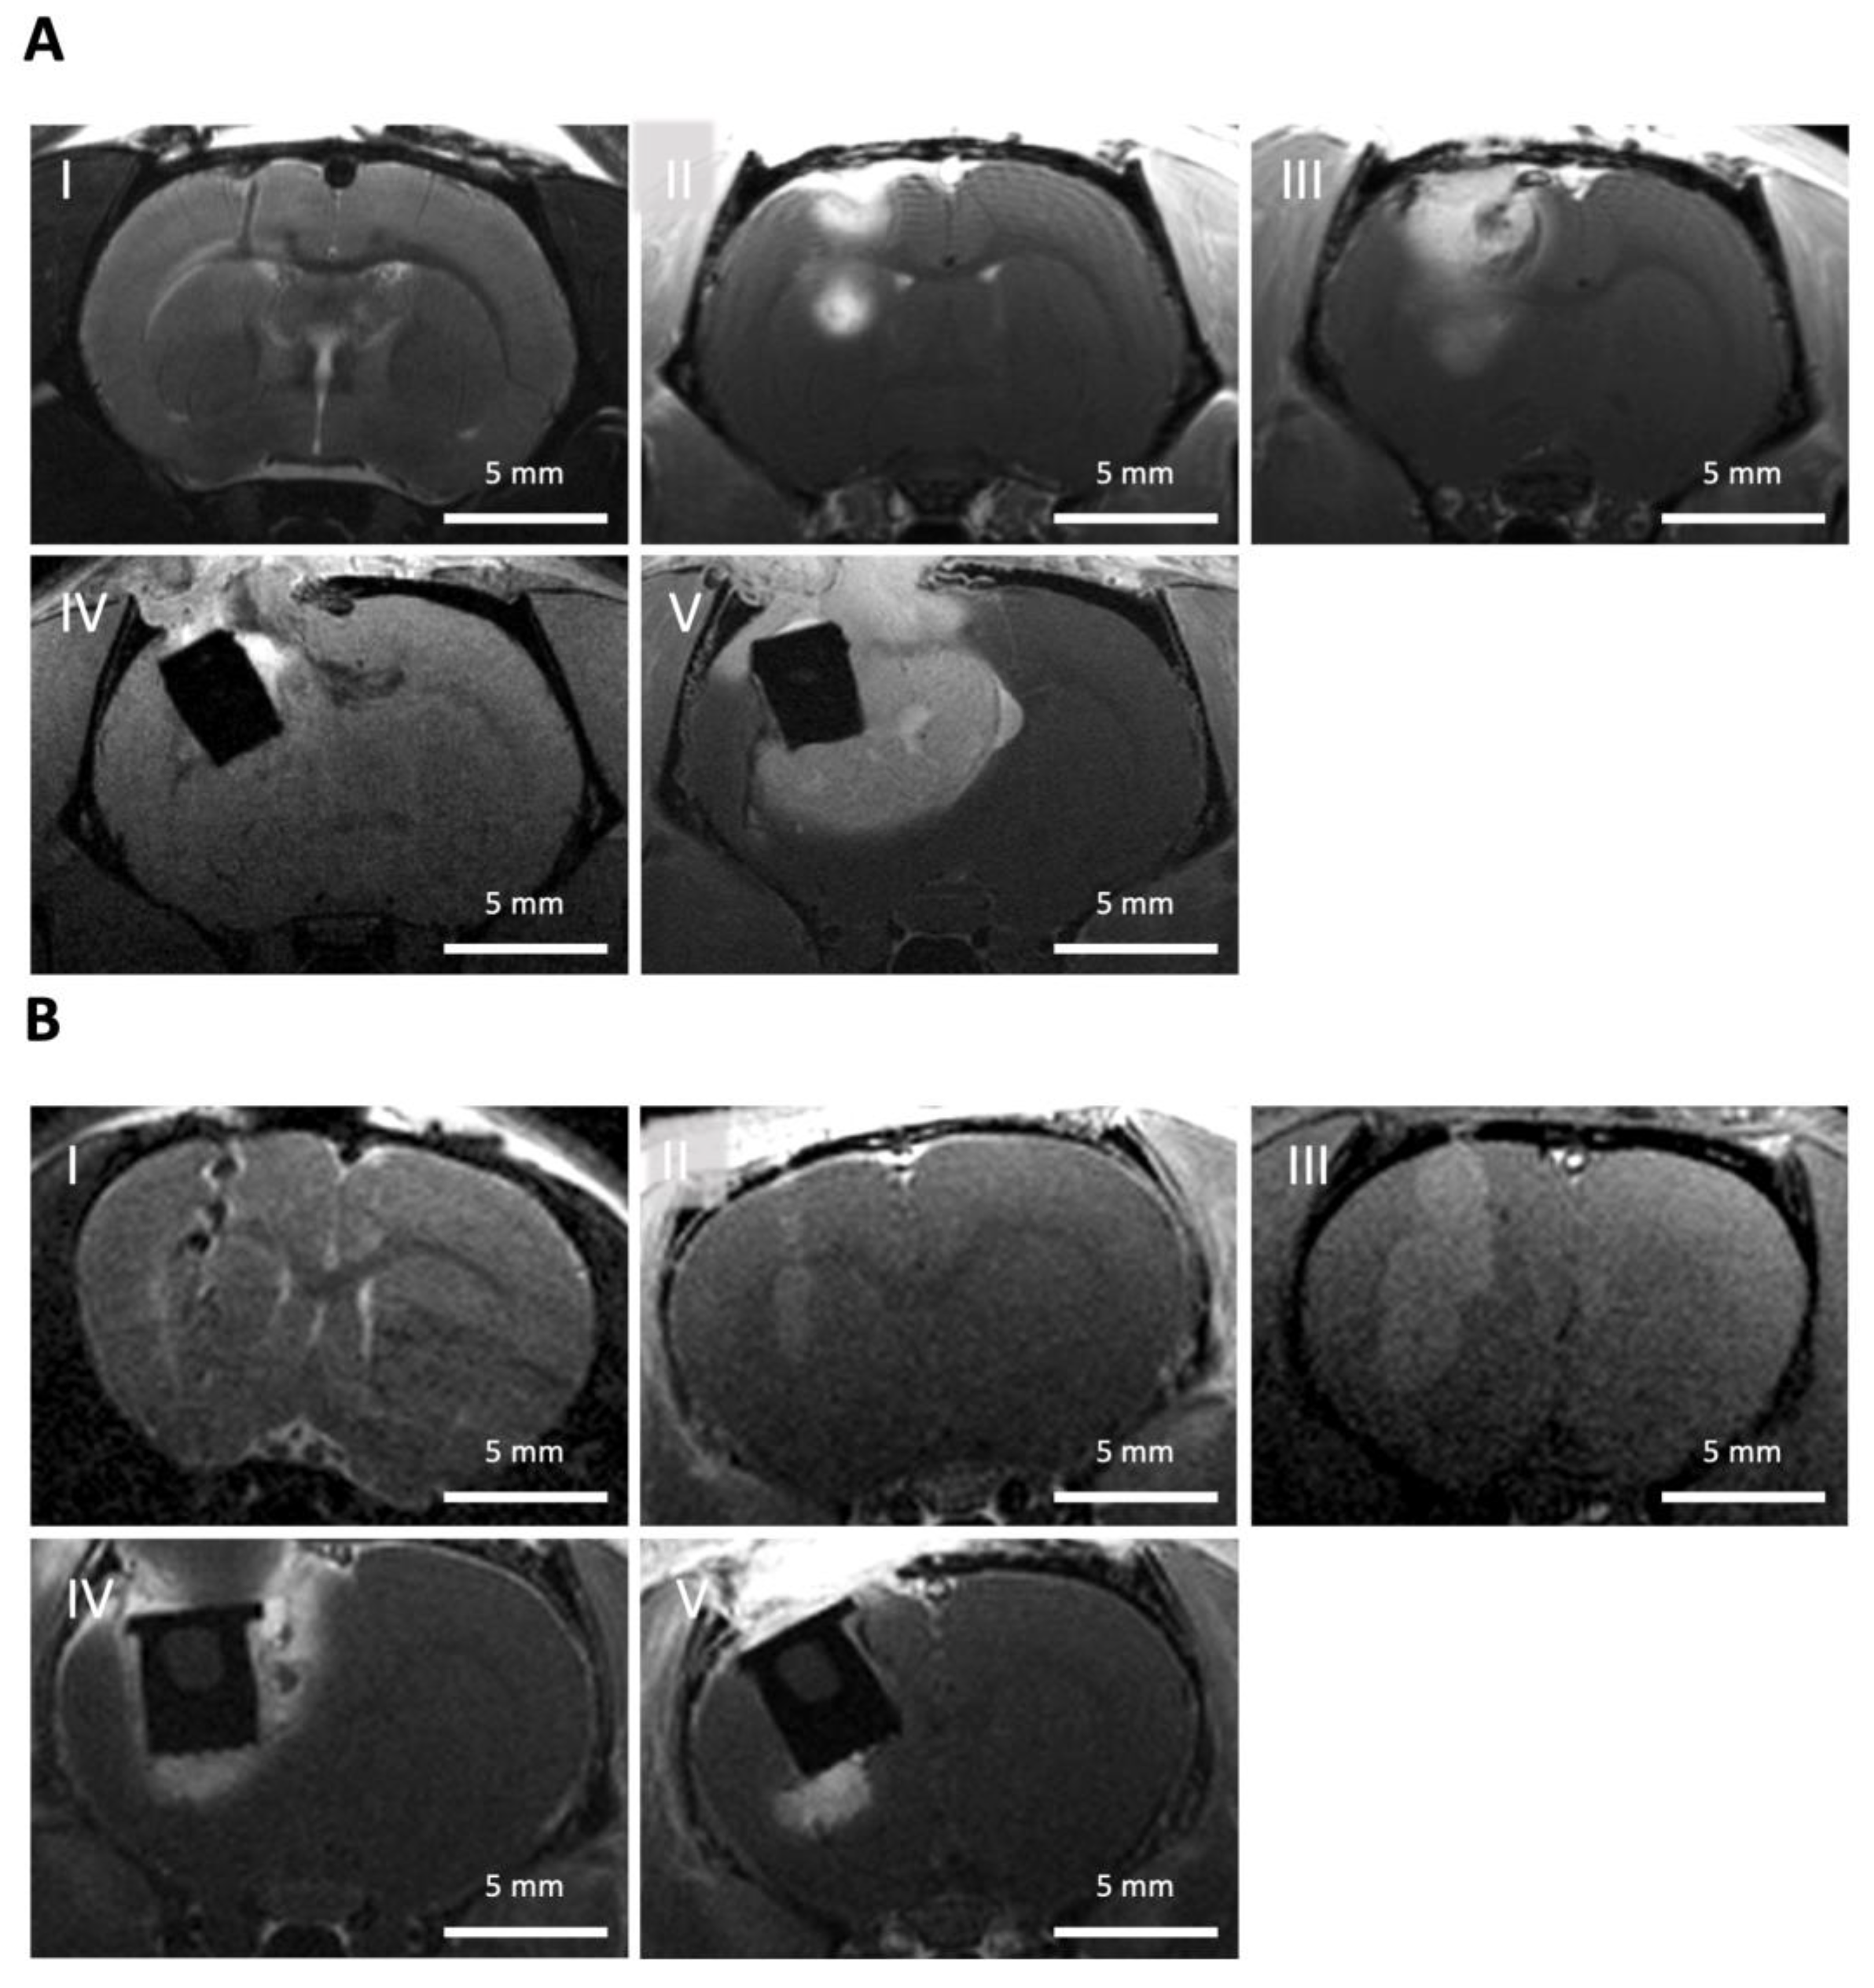

3.5. Monitoring of the Animal Experiment Using MRI

In order to monitor tumor growth, document the postoperative status, and assess the amount of residual tumor after resection, regular (mostly weekly) MRIs were carried out (Figure 7). During the MRI, the sedated animals were placed on a heating mat and monitored by breathing rate. The standardized positioning of the animals (prone position, head first in a straight position), standardized selection of adequate MRI sequences (details given in Section 2.4), and standardized positioning of the scanned slices were decisive. In order to better identify the tumor tissue, an intravenous contrast agent was administered, and a (residual) tumor was thereby defined as an intensely enhancing mass on T1-weighted images.

Figure 7. Monitoring of the animals with high-resolution Magnetic Resonance Imaging (MRI). (A) Wistar rat: (I) Coronal T2-weighted MRI showing the injection path (black) from the inoculation of C6 tumor cells. T1-weighted, post-contrast MRI was used to monitor tumor growth (bright) after (II) 14 days and (III) 21 days of inoculation. (IV) Postoperative MRI revealing the implant (black) loaded with Ringer’s solution and surrounding residual tumor tissue (bright; T1-weighted image). (V) Monitoring of tumor progression surrounding the implant (T1-weighted, post-contrast MRI); (B) Athymic rat: (I) Inoculation of patient-derived glioma stem-like cells (coronal T2-weighted MRI). Tumor growth (II) 4 and (III) 9 weeks after inoculation, as well as (IV) residual tumor tissue after partial resection and introduction of the implant loaded with Ringer’s solution and (V) tumor progression around the implant 2 weeks after partial tumor resection (coronal T1-weighted, post-contrast MRI).